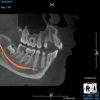

(10.) Tooth No. 31 in this 14-year-old patient does not exhibit caries. It is a “ghost tooth.” The lack of a periapical pathosis, the location of the tooth relative to the inferior alveolar nerve, and the development of tooth No. 32 are all visible in the CBCT image. These factors will aid the clinicians in developing a treatment plan to deal with this unusual internal resorption case.

Figure 10